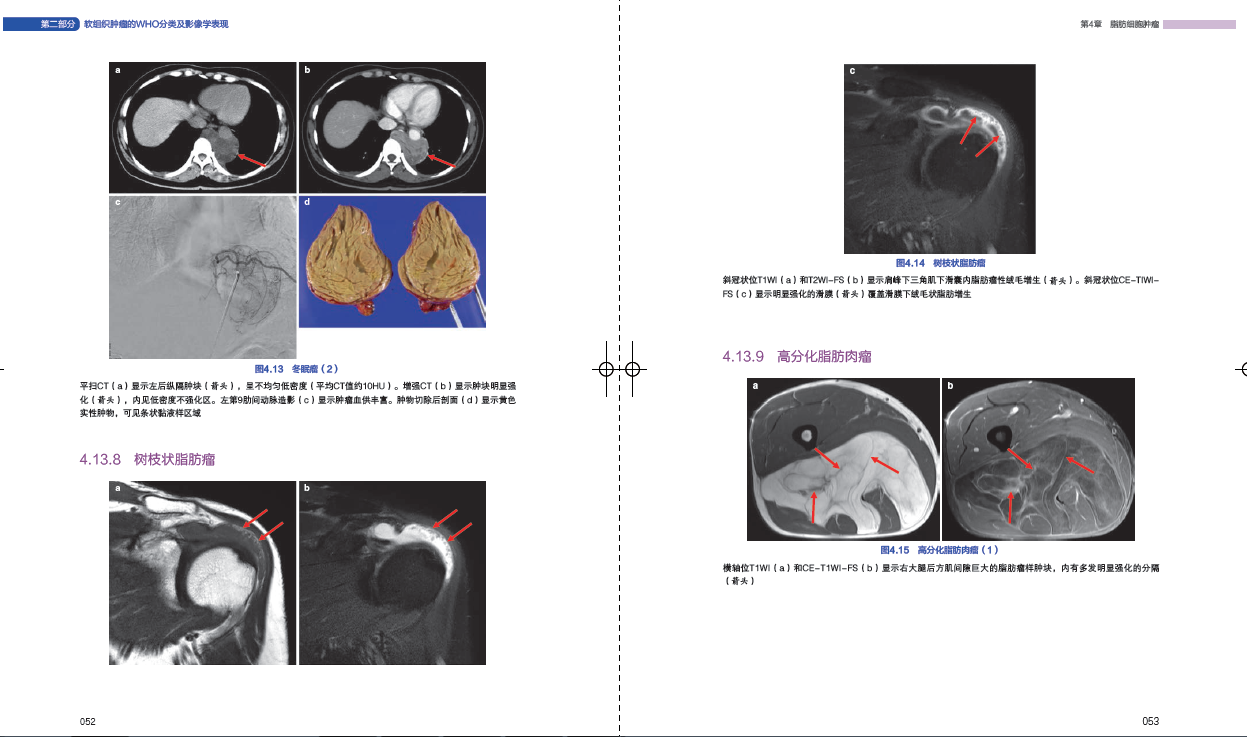

47 冬眠瘤041

48 树枝状脂肪瘤041

49 非典型脂肪瘤样肿瘤/高分化脂肪肉瘤041

413 示例:脂肪细胞肿瘤044